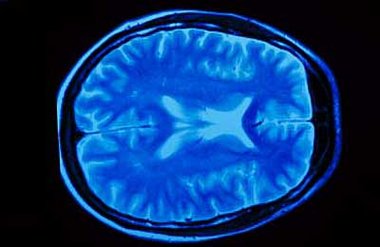

Unser Gehirn ist im Inneren des Schädels in einer Flüssigkeit (Liquor) gelagert und so eigentlich recht gut geschützt. Schlägt der Kopf allerdings mit großer Geschwindigkeit auf einen harten Gegenstand, kann das Hirn schwappend trotzdem an den Schädelknochen prallen und daraus eine vorübergehende Störung der Gehirnfunktionen resultieren.